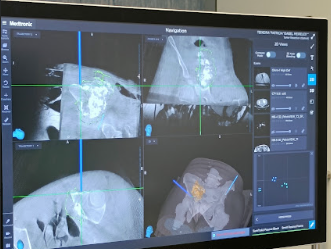

O Centro Hospitalar Universitário de Santo António realizou, recentemente, uma intervenção inédita em Portugal, a primeira cirurgia de resseção tumoral assistida por navegação computorizada.